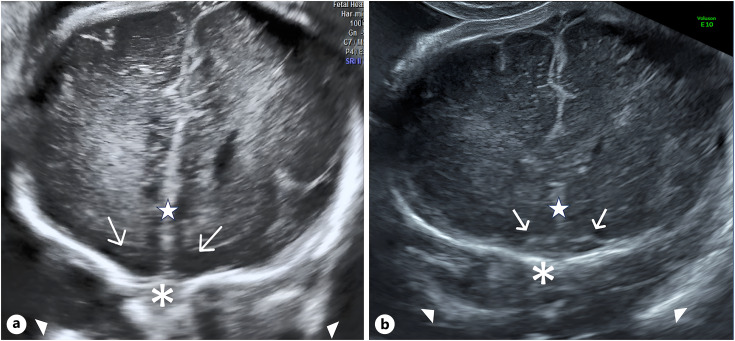

Methods: We prospectively evaluated OS development in fetuses diagnosed with CHDs from 2017 to 2021. Neurosonography was performed using transabdominal and transvaginal approaches after 30 weeks of gestation. OS assessment was conducted in the trans-frontal coronal plane, classifying their appearance as fully developed, hypoplastic, or absent. Abnormal OS cases underwent MRI and trio-based clinical exome sequencing (CES).

Results: The study included 147 fetuses with CHD. Abnormal OS were found in 4 fetuses (2.7%) which also exhibited other additional anomalies. OS were absent in cases 1-3 and hypoplastic in case 4. MRI confirmed OS abnormalities in all cases, and trio-based CES identified a CHD7 gene mutation in cases 1, 2, and 4, supporting the diagnosis of CHARGE syndrome. Case 3 had normal trio-based CES results. No other CHARGE syndrome cases were diagnosed postnatally among the cases with normal OS.